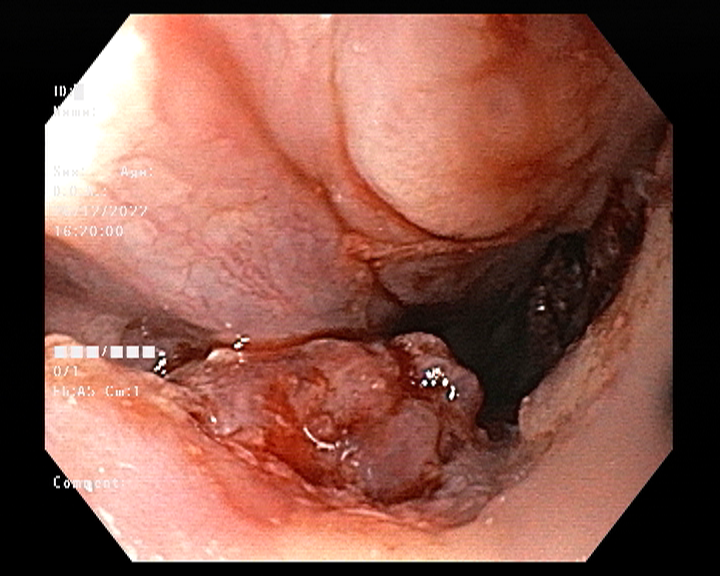

Endoscopy and colonoscopy are safe and accurate procedures used to directly examine the digestive tract and detect the root cause of chronic acidity, GERD, abdominal pain, bleeding, and bowel irregularities. These minimally invasive tests help identify ulcers, inflammation, infections, polyps, strictures, and early cancerous changes.

At Sapphire Gastroenterology Center, modern endoscopic equipment ensures precise diagnosis and, when required, therapeutic intervention during the same procedure. Based on findings, targeted treatment plans are created, including medication, diet guidance, and preventive strategies. Early diagnosis through endoscopy and colonoscopy plays a crucial role in preventing serious complications and improving long-term digestive health.